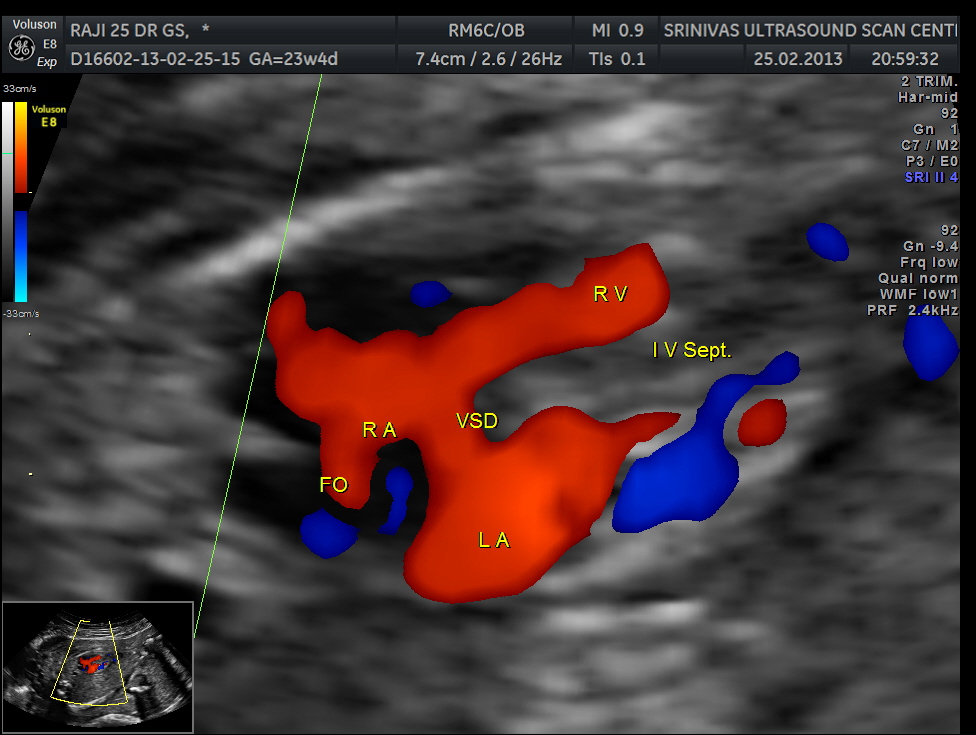

apart from foramen ovale flow , VSD is seen

Ventricular septal defect seen